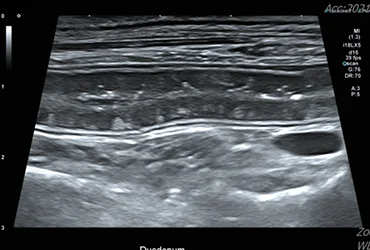

1. 복부 초음파 검사

간, 담낭, 췌장, 위장관 등의 구조적 이상을 평가하여 질환의 유무를 확인합니다. 실시간 영상으로 장기의 형태, 크기, 내부 구조를 정밀하게 모니터링합니다.

비침습적이고 안전하게 소화기계 문제를 스크리닝하고 진단합니다.